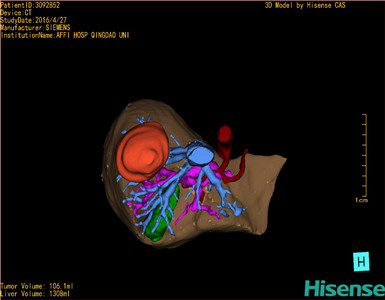

CT结果输入海信CAS系统后行3D重建及手术规划后,于2016-5-14全麻下行“肝VII+VIII段切除术”手术治疗:

将0.625mm双源薄层CT资料的静脉期和动脉期Dicom格式文件导入海信CAS系统。

通过调节窗宽窗位调整CT序号,对肿瘤,肝实质,胆囊,下腔静脉,肿瘤,肝动脉、门静脉及肝静脉等进行三维重建;系统自动计算肿瘤体积和肝脏体积。

模拟手术操作,自动计算切除肿瘤体积。肝脏体积为1308ml,肿瘤体积为106.1ml,肿瘤体积为肝脏体积的8.1%,通过比对40-50岁正常肝脏体积为1368.38±279.24 ml,通过术前模拟手术,精准判断切除后剩余肝脏体积能耐受,避免肝衰竭发生。

术前三维重建:

重建图片